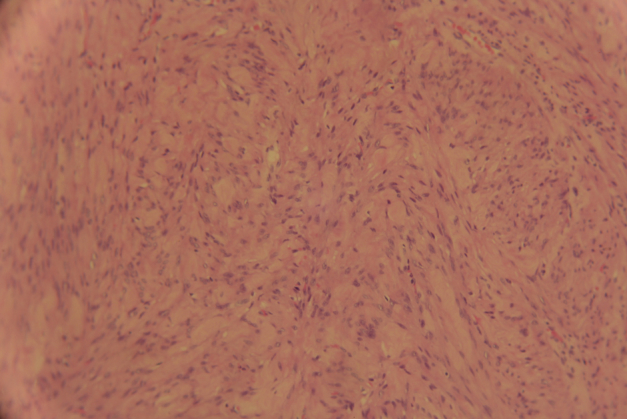

The patient was discharged on postoperative day 4. Histology of the paraffin specimen confirmed the diagnosis of a benign leiomyoma (Figure 3, Figure 4).

Figure 3.

Tumor showing dense aggregation of spindle-shaped cells (HE ×100).